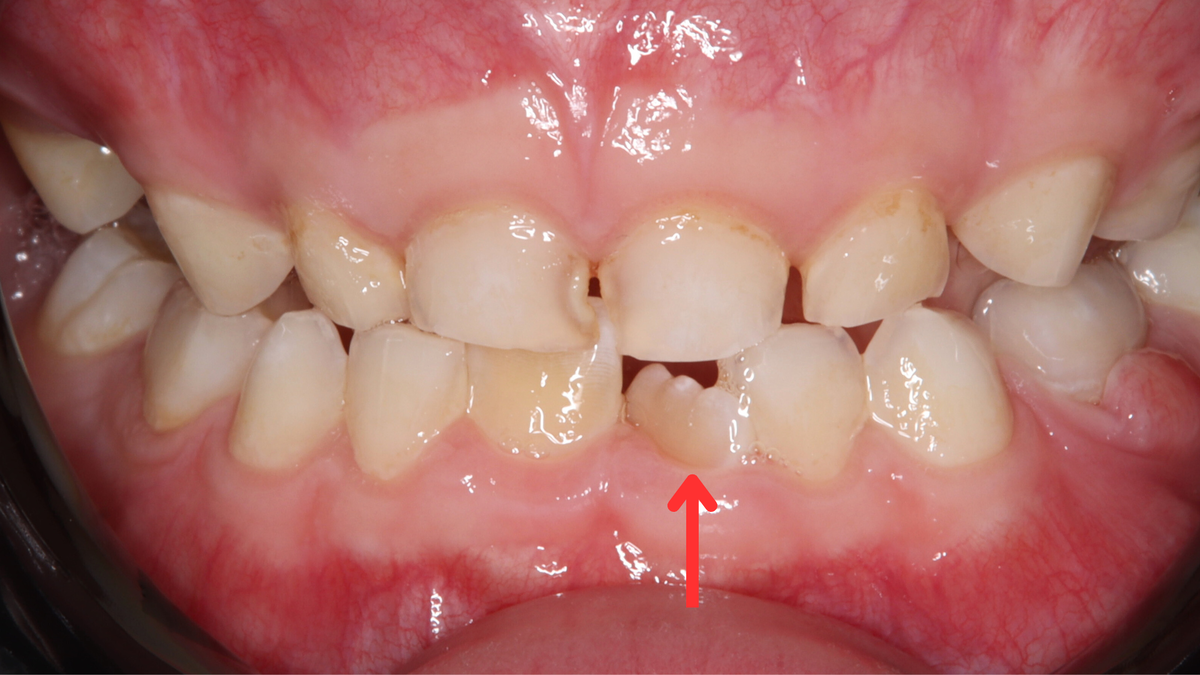

Тортоаномалия — это патология прикуса, при которой положения зуба меняются по вертикали, вокруг своей оси. Поворот зуба бывает разной степени: от нескольких градусов до 90˚. В редких случаях он может достигать 180˚, из-за чего передняя поверхность зуба оказывается обращённой внутрь.

В период сменного прикуса многие родители начинают озадачиваться: на смену аккуратным молочным зубам приходят постоянные — значительно более крупные, и им зачастую просто не хватает места в ещё маленькой челюсти. Из-за этого они могут прорезываться под углом или поворачиваться вокруг своей оси — так появляется тортоаномалия.

Тортоаномалия чаще всего возникает у детей в период сменного прикуса.